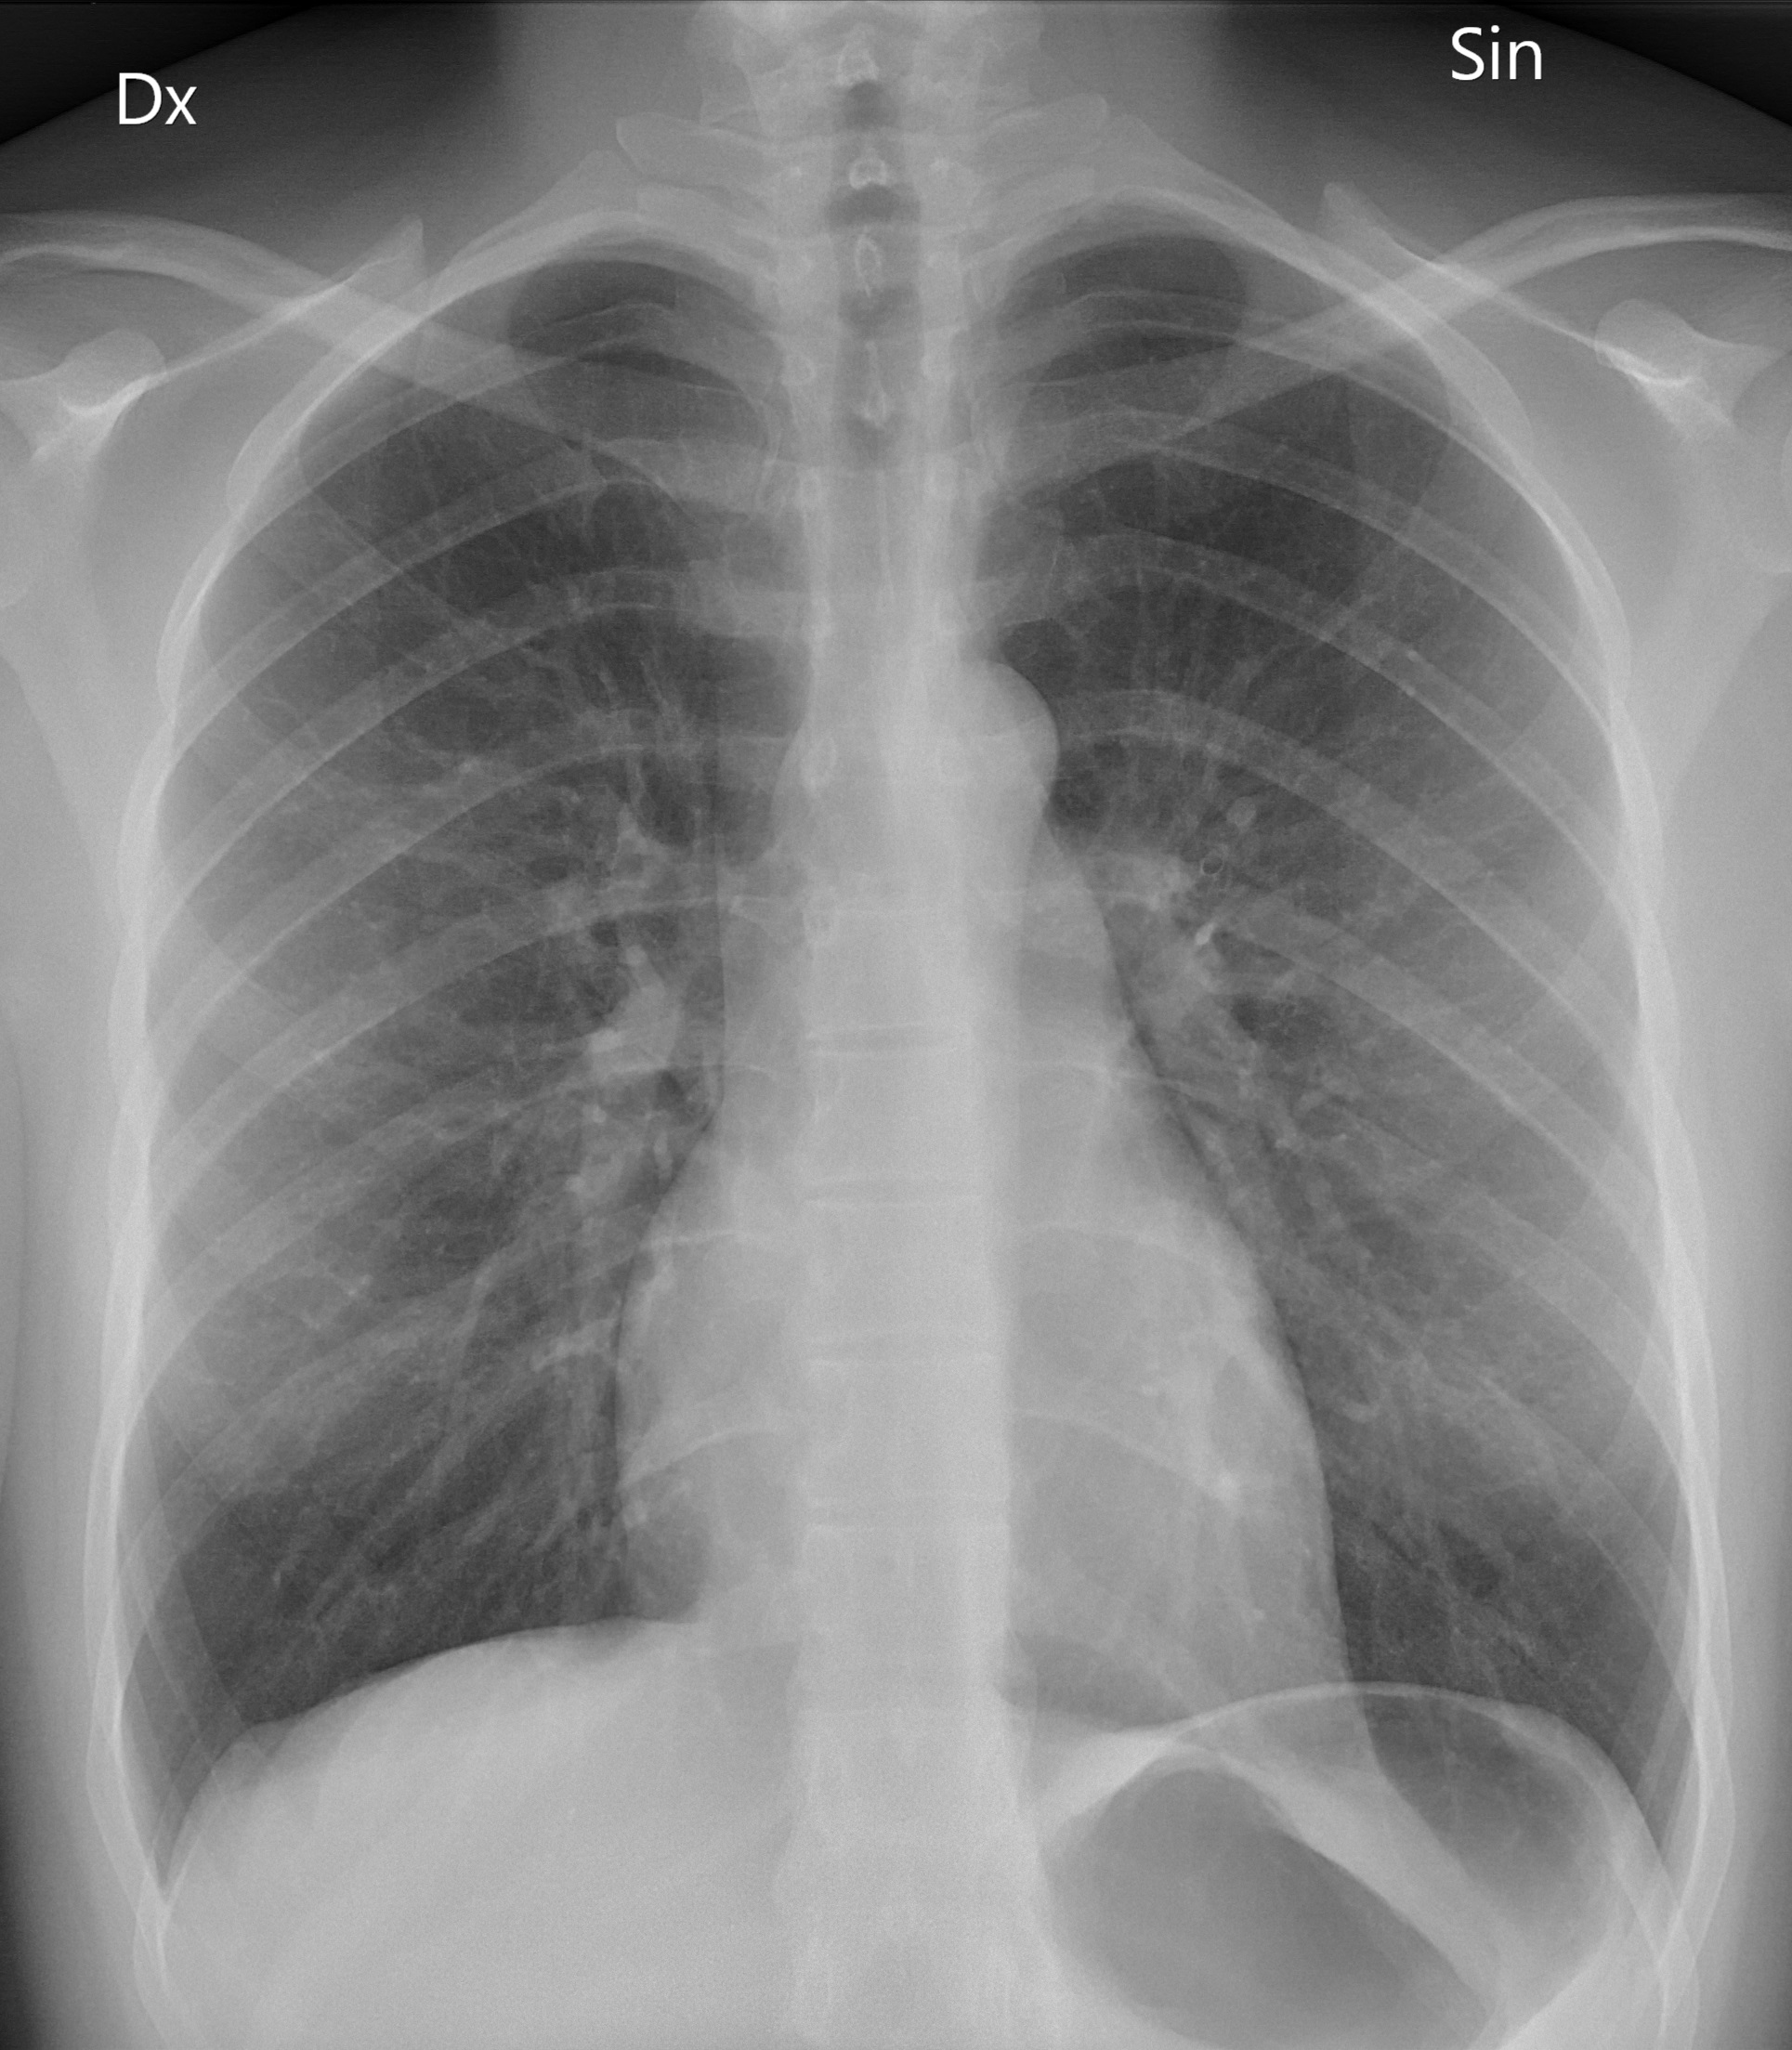

正常胸部X射线正位(PA)片:可见心影、肺野、肋骨和膈肌等正常解剖结构

- 正常胸部X射线:Wikimedia Commons - Normal PA chest radiograph,CC BY-SA